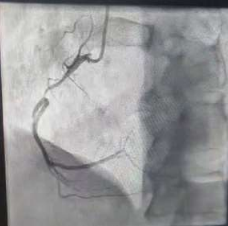

60 year old male known diabetic, hypertensive and dyslipidaemic presented with unstable angina, Coronary angiogram revealed Mid RCA pre crux lesion of 80-90% stenosis and PDA and PLV arising from Mid RCA (Fig 1). It was an angulated bend post bifurcation and hence Fielder FC wire support was taken to easily manipulate the vascular bifurcation (Fig 2) and successful PTCA+ stent to Mid RCA was done with 3x24mm Yukon choice flex stent (Fig 3& 4). TIMI III flow was achieved and post procedure period was uneventful.

FIG 1: Early bifurcating dominant RCA, Pre crux 90% stenotic lesion, with acute angled bifurcation